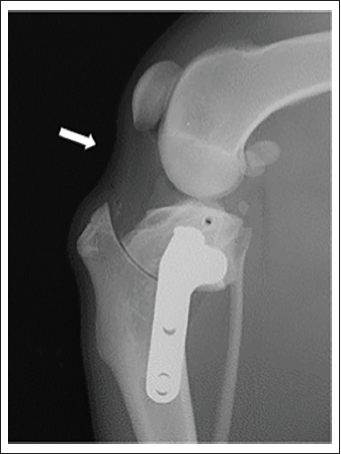

In our study, TPLO demonstrated downward traction of the patella but to a lesser extent than CCWO. Previous studies have reported decreasing PLL:PL value after TPLO (Guénégo et al., 2021). In an ex vivo study, Pozzi et al. (2013) reported the effects of TPLO on the patellofemoral joint, including the distal and caudal displacement of the patella relative to the femur as well as a decreased patellar tilt angle. Additionally, Jay et al. (2019) reported a postoperative decrease in the PLL. Specifically, the change in the PLL could have led to the downward traction of the patella, which could be attributed to the shortening of the distance between radiological landmarks rather than the actual shortening of the PLL. In our study, there was a postoperative caudal deflection of the patellar ligament (Fig. 4). As shown in Figure 3, the tibia widens as the bone rotates, and the cranial side of the proximal fragment sinks downward in TPLO. Consequently, the patellar ligament and surrounding soft tissues may have been pulled and deflected. In addition, a change in the patellar axis may have occurred with patellar ligament deflection, as Pozzi et al. (2013) reported, which may have affected the PLL. Consequently, the patella was considered to have moved mildly downward.

Fig. 4. Deflection of the patellar ligament. Mediolateral radiograph of the stifle joint after TPLO. The patellar ligament is caudally deflected (white arrow). TPLO.